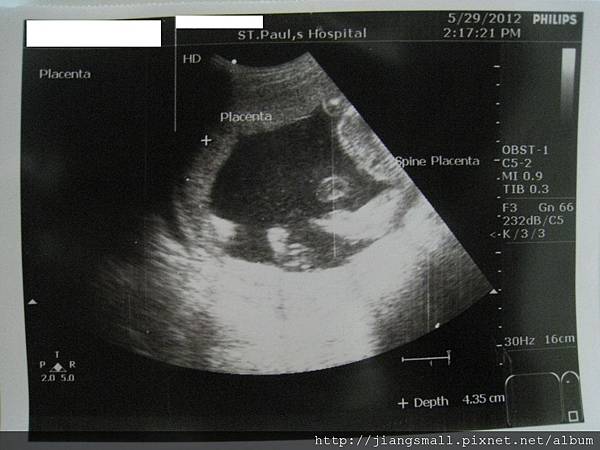

第三次產檢

Bebe一樣在裡面手舞足蹈,雖然肚子沒很大,但是醫生說大小都正常。可是,我肚子也太小了吧…五個月了說…。體重倒是很正常的每週0.5kg增加。沒有特別多…,看來要再多吃ㄧ點了。

這次的超音波照片真不清楚,明明照了很多張,但是都貼到某一份文件上,不是給我們的文件上…,下次應該要多要幾張。